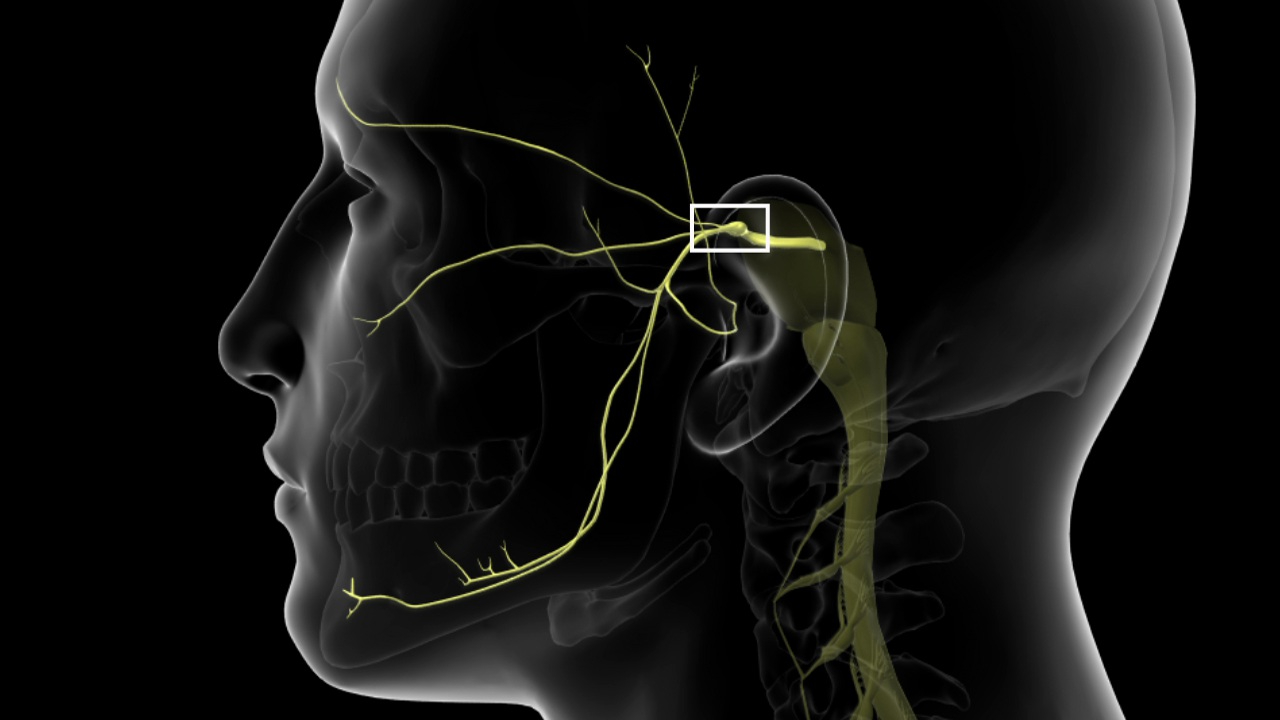

حقن العمود الفقري بالتردد الحراري ، والمعروف أيضًا باسم بضع العصب